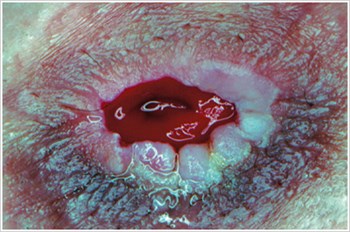

Pyoderma Gangrenosum

Description/Causes:

An inflammatory skin disease often seen in patients with inflammatory bowel disease ( IBD ) such as Crohn's disease or ulcerative colitis.

Symptoms:

- Irregularly shaped, red, painful, infected ulcers, with red-to-purple rolled margins; appear on legs, buttocks, face, and peristomal area.